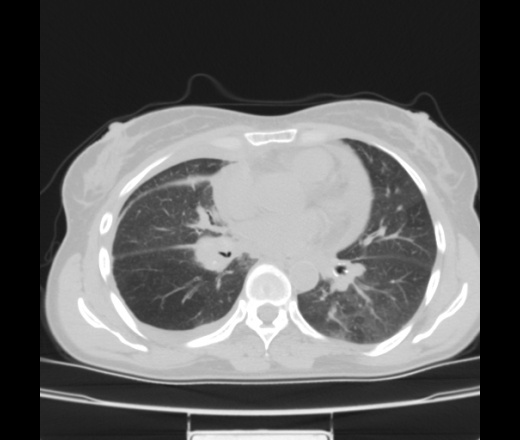

Женщина 55 лет. Жалобы на одышку, кушель с мокротой белого цвета, повышение температуры до 38, слабость, потливость, похудение. Больна в течение месяца. Лечилась в стационаре ЦРБ с пневмонией справа. Из выписки ОАК СОЭ-55, эр-лей-тромб - в норме. Мокрота на БК -. Анализ плевральной жидкости лейкоциты 12-13 , эритроциты измененые и неизмененые, клетки мезотелия.

За tbc c поражением внутригрудных л/узлов, правосторонним плевритом. Экс.перикардит. Признаки сердечной недостаточности.

Как второй вариант сочетание ЛГМ  и tbc, но тогда вопрос об имунном статусе.